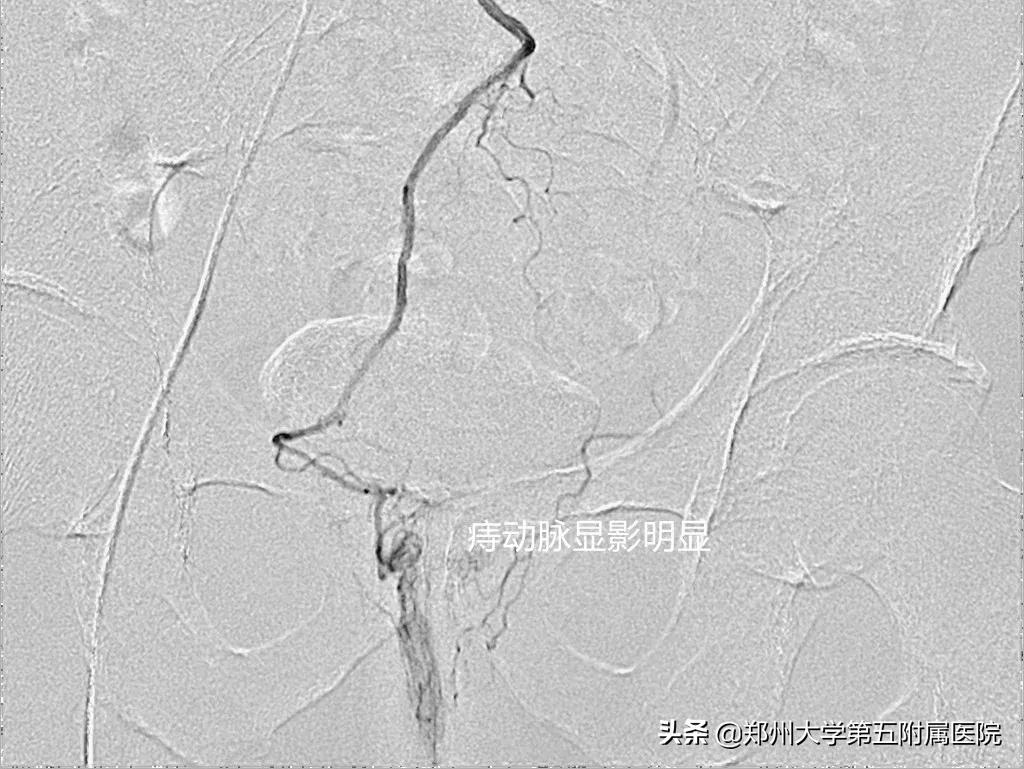

入院后,介入科吕军主任详细评估患者病情后,决定采用 直肠上动脉造影并部分栓塞术 来进行治疗。完成手术仅半小时,术后4小时患者即可下床活动,术后第2天肛门不适感明显缓解。出院时,张先生此前的疑虑都烟消云散。术后2个月随访,未再便血,无任何不适,并给予高度称赞。

▲ 栓塞前后对比

肛门直肠的血管结构非常复杂,而这正是介入治疗的优势所在。该手术是利用导管经股动脉导入后进行造影检查,全面清楚地分辨“痔动脉”的起源、走形方向,然后再将更细的微导管插入“痔动脉”,在血管内注入栓塞材料,阻断痔动脉的血流,从而达到痔的治疗目的。